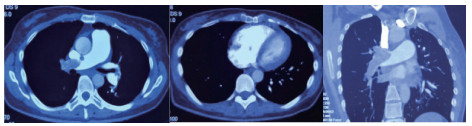

例2 72岁,男性。主因“活动后气短3 d,加重伴有晕厥1次”住院。既往体健,否认制动史及手术史。入院查体:神志清楚,体温36℃,血压120/70 mmHg,脉搏110次/min,呼吸22次/min,脉氧93%(安静,空气氧),轻度乏氧征。双肺呼吸音清,未闻及干湿性啰音。心率110次/min,心律齐,P2 > A2,心界无扩大,无杂音。腹软,无压痛,肠鸣音正常,双下肢无浮肿。神经系统查体未见异常。血气分析(安静,空气氧)提示pH 7.457,PaCO2 26.7 mmHg,PaO2 74.0 mmHg,SaO2 95.5%;D-Dimer 13 743 ng/ml;FDP 175.060 μg/mL,FBG 1.990 g/L;PLT:224 G/L;cTnI 0.04 ng/mL,BNP 666 pg /mL;ALT 15 U/L,AST 27 U/L,CREA 103.3 mmol/L,血Na+、K+、Cl-:正常范围;UCG提示:右心增大,肺动脉主干增宽(28 mm),三尖瓣反流(中-重度),反流面积11.5 cm2,TI法估计SPAP为50 mmHg、左室舒末内径38 mm、左心功能稍减低E波/A波= 60/40 cm/s,未见节段性室壁运动障碍;双下肢静脉超声提示右侧股总、股深、股浅、腘静脉及双侧小腿肌间静脉丛血栓形成。心电图(图 5所示)提示窦性心动过速;CTPA提示双肺主干明确充盈缺损(图 6所示)。入院诊断:急性PE(中高危)。给予低分子肝素重叠华法令抗凝治疗。D-Dimer由入院时13 743 ng/mL分别降至第2天10 000 ng/mL,第3天9 000 ng/mL和第四天的5 000 ng/mL。住院第4天开始出现纳差、恶心未吐,复查心电图提示窦性心动过速,SⅠQⅢTⅢ,胸导T波加深(如图 7所示)。入院第5天床上排便后出现呼吸急促,储氧面罩吸氧(Flow 10 L/min)维持氧合78%(当天INR 2.02),15 min后出现血压、心率下降至消失,心外按压始终无自主呼吸及心律恢复,因家属放弃系统溶栓治疗,抢救2 h无效宣告患者临床死亡。回顾入院后连续复查的心电图提示右心负荷有逐渐加重及胸前导联缺血加重的倾向;UCG同样证实右心室内径呈进行性增大的趋势(分别为入院时的右心房31 mm×47 mm、第2天28 mm×40 mm和第4天的54 mm×60 mm)。

| 图 6 入院时CTPA提示双肺主干明确充盈缺损 |

| 图 7 入院第4天病情变化时心电图变化。窦性心动过速,SⅠQⅢTⅢ,胸前导联T波加深 |